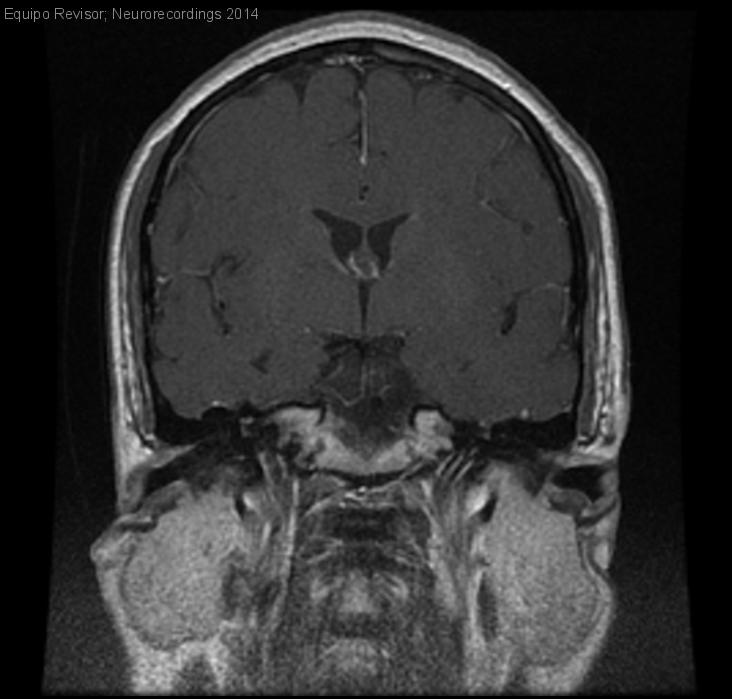

Meningioma del Seno Cavernoso

Mujer | 39 años

Diagnóstico final: Meningioma

Neurología: Cefalea

Consulta por tres meses presenta dolor constante, con unas 4-5 exacerbaciones al día, en ramas II y III del trigémino derecho, que empeora al comer pero no al hablar. Se inicia Gabapentina y tras...